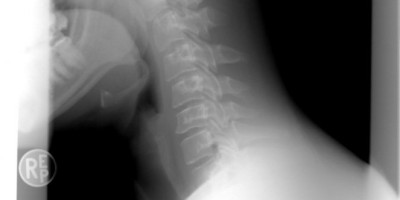

Najčešći oblici artritisa su osteoartritis i reumatoidni artritis. Iako se bolest može dobiti u bilo kom starosnom dobu, obično se javlja kod osoba starijih od 45 godina, a češći je kod žena.

Artritis počinje jutarnjom ukočenošću u zglobovima, što se prvo registruje na zglobovima prstiju šake (ne možete da popijete jutarnju kafu s lakoćom). Kada se zglobovi razmrdaju, simptomi prolaze do sledećeg jutra.

Ubrzo nakon jutarnje ukočenosti javlja se bol, nekad i otečenost, koji su u početku prisutni samo povremeno ili prilikom određenih kretnji u zglobu, da bi kasnije prešli u hronično stanje. Ako se bolest ne leči adekvatno (naročito reumatoidni artritis), može da dovede do invaliditeta, pa čak i do smrtnog ishoda.